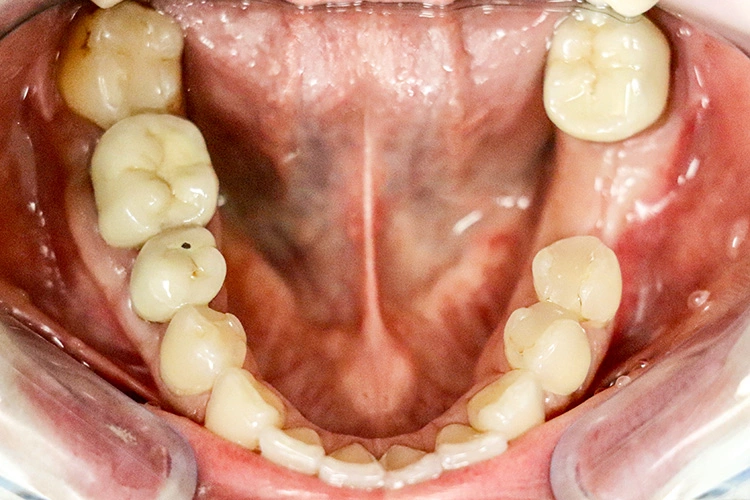

Die Dokumentation des Implantatsitzes erfolgte mit einer postoperativen Panoramaschichtaufnahme (Abb. 16). Nach der gedeckten Einheilung erfolgte im Juni 2021 die geschlossene Implantatabformung mit Impregum. Abbildung 17 bis 25 zeigt den Ablauf von der Inzision drei Monate nach Implantation bis zum Einsetzen des Hybrid-Abutments mit Titan-Klebebasis und Zirkonaufbau bis zur finalen Zirkonkrone, die aufgrund einer Erkrankung der Patientin etwas später als vorgesehen im Juli 2021 eingegliedert werden konnte. Die Versorgung der insuffizienten Einzelkrone 47 erfolgt auf Patientenwunsch zu einem späteren Zeitpunkt.